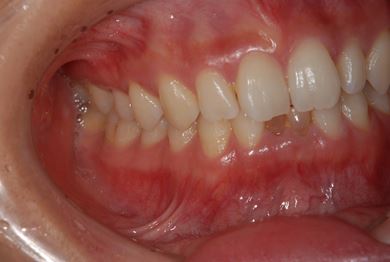

| 性別/年齢 | 女性 / 28歳 | ||||||||||||||||||||||||||||||||

| 主訴 | 下前歯の色が気になるので、ホワイトニングかセラミック治療できれいにしたい。(下前歯2本は乳歯でした) | ||||||||||||||||||||||||||||||||

| 治療方針 | 下顎前歯、乳歯を抜歯し、セラミック治療にて審美的回復を行う。 | ||||||||||||||||||||||||||||||||

| 治療内容 | エンプレスジルコニアフレームオールセラミッククラウンブリッジ4本 | ||||||||||||||||||||||||||||||||